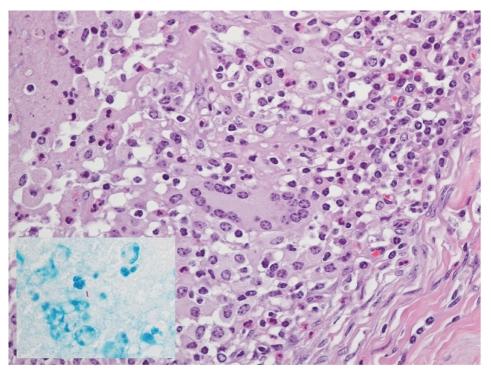

In 2009, Mycobacterium bovis infection was detected in a herd of 60 elk (Cervus elaphus) and 50 fallow deer (Dama dama) in Nebraska, USA. Upon depopulation of the herd, the prevalence of bovine tuberculosis (TB) was estimated at ∼71-75%, based upon histopathology and culture results. Particularly with elk, gross lesions were often severe and extensive. One year ago, the majority of the elk had been tested for TB by single cervical test (SCT), and all were negative. After initial detection of a tuberculous elk in this herd, 42 of the 59 elk were tested by SCT. Of the 42 SCT-tested elk, 28 were TB-infected with only 3/28 reacting upon SCT. After SCT, serum samples were collected from the infected elk and fallow deer from this herd at necropsy and tested by three antibody detection methods including multiantigen print immunoassay, cervidTB STAT-PAK, and dual path platform VetTB (DPP). Serologic test sensitivity ranged from 79 to 97% depending on the test format and host species. Together, these findings demonstrate the opportunities for use of serodiagnosis in the rapid detection of TB in elk and fallow deer.